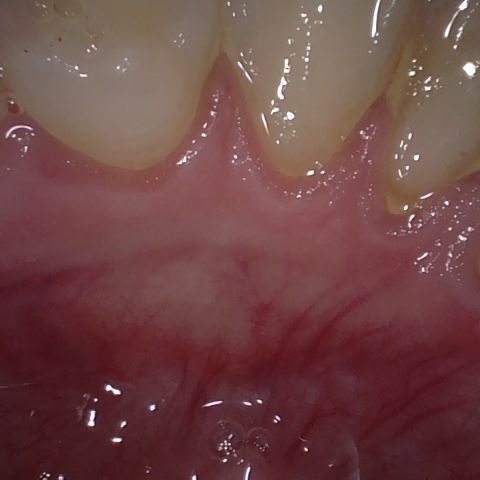

Annotated as "Good"